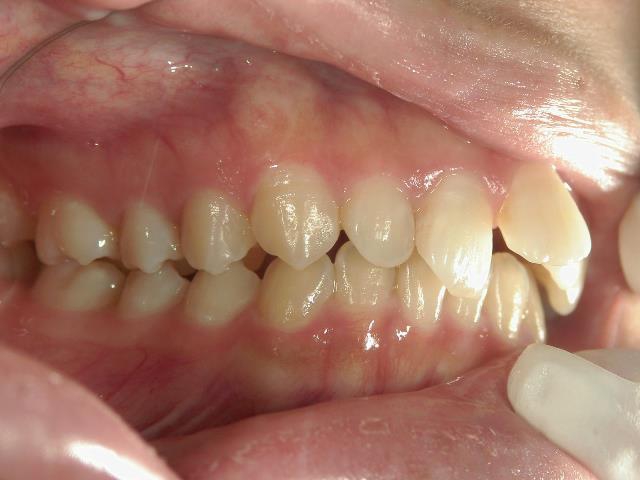

矯正歯科 治療前 左